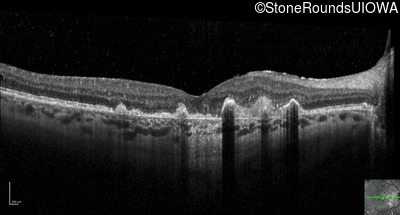

Visit at age: 60 years (Visit 3)

Optical Coherence Tomography - Right - 20/150

Exemplar / OCT Stack

OCT Stack

Infrared Fundus Photograph - Right - 20/150

Exemplar